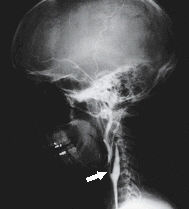

Refer to this picture for question 3.

3. The above condition can be caused by: